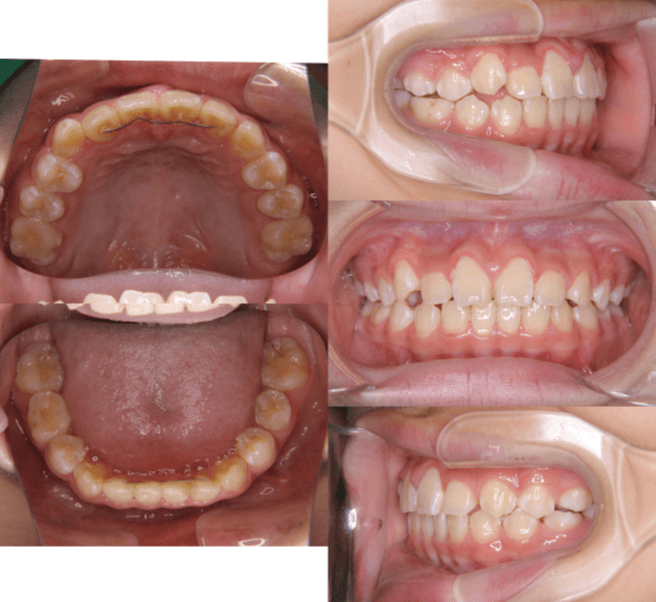

上歯前突+叢生症例 成長期

主訴 | 口元の突出感と歯並びが気になり、将来的な咬合状態を整える目的で来院された患者様です。 |

---|---|

診断結果 | 11歳1か月の女性。骨格的には日本人標準に近く、歯性の上顎前突および叢生が認められました。上下顎ともに歯列のスペース不足があり、永久歯の萌出や歯列の整列に支障をきたす可能性があると診断されました。 |

治療内容 |

|

治療後の経過 | 動的治療終了後は、上下顎の歯列が整い、口元の突出感と叢生が改善されました。審美的・機能的なバランスが取れた状態となり、現在は取り外し式リテーナーを使用し、保定期間に移行しています。 |

治療期間 | 動的治療期間:2年6か月 通院回数:25回 |

治療費用 | 720,000円 |